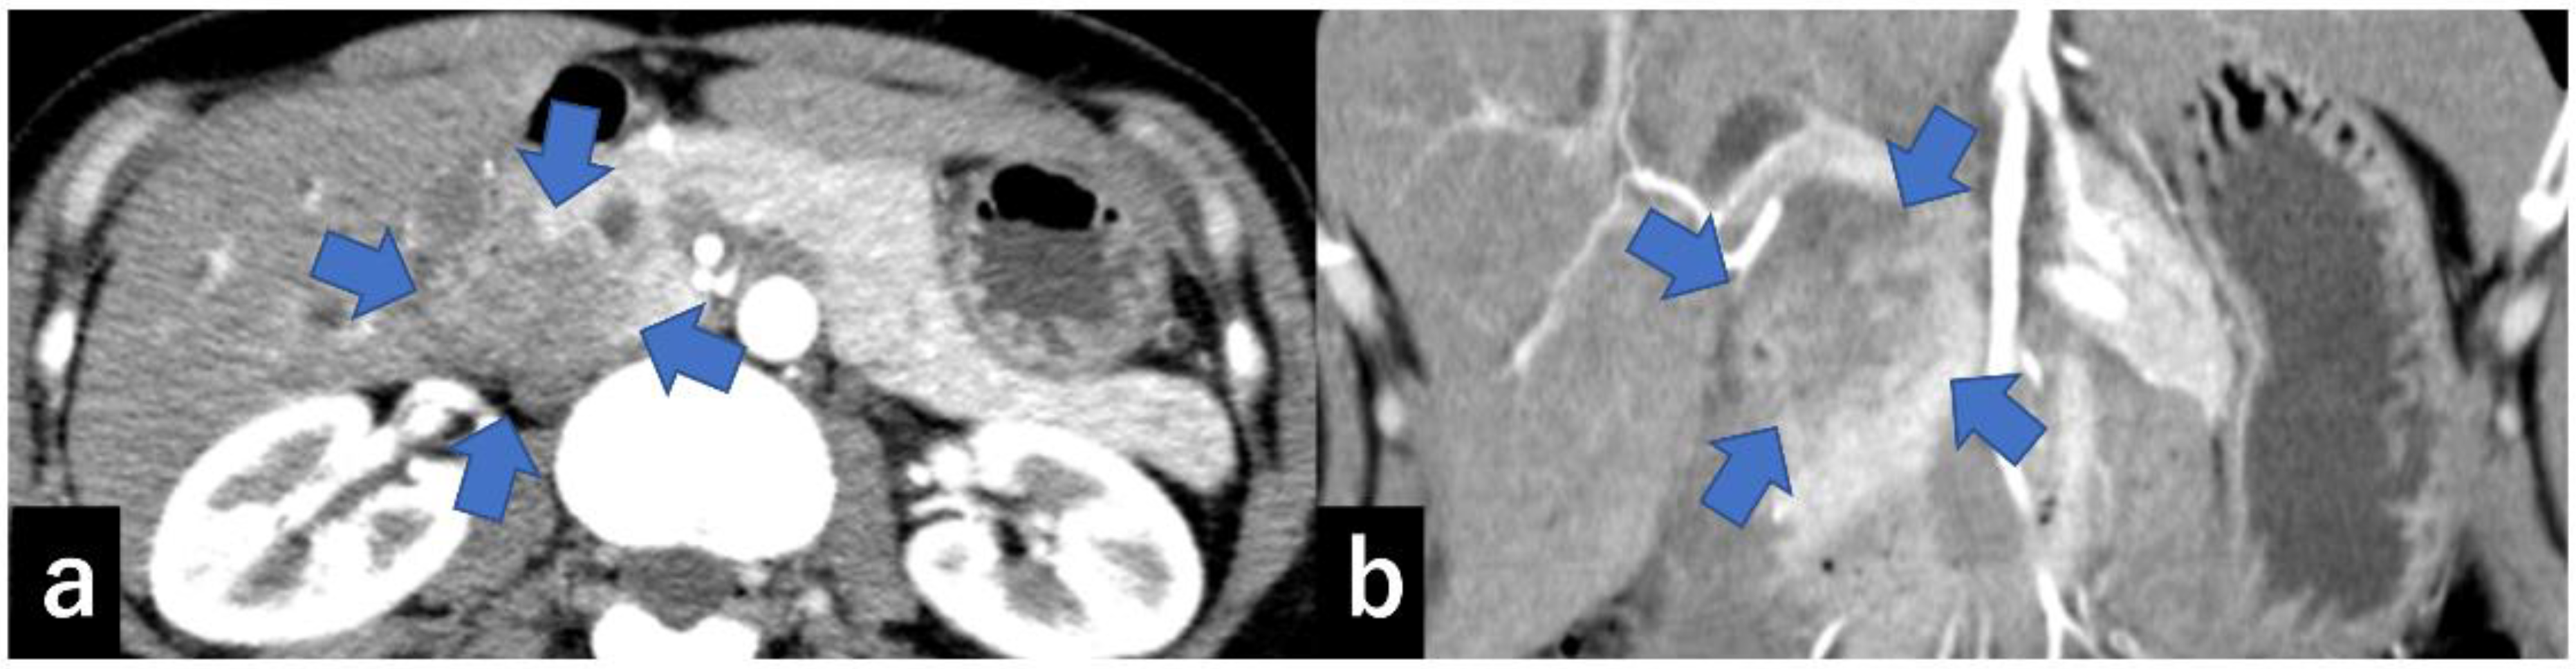

- Miura, S.; Takikawa, T.; Kikuta, K.; Hamada, S.; Kume, K.; Yoshida, N.; Tanaka, Y.; Matsumoto, R.; Ikeda, M.; Kataoka, F.; et al. Focal Parenchymal Atrophy of the Pancreas Is Frequently Observed on Pre-Diagnostic Computed Tomography in Patients with Pancreatic Cancer: A Case-Control Study. Diagnostics 2021, 11, 1693. [Google Scholar] [CrossRef] [PubMed]

- Toshima, F.; Watanabe, R.; Inoue, D.; Yoneda, N.; Yamamoto, T.; Sasahira, N.; Sasaki, T.; Matsuyama, M.; Minehiro, K.; Tateishi, U. CT abnormalities of the pancreas associated with the subsequent diagnosis of clinical stage I pancreatic ductal adenocarcinoma more than 1 year later: A case-control study. AJR Am. J. Roentgenol. 2021, 217, 1353–1364. [Google Scholar] [CrossRef]